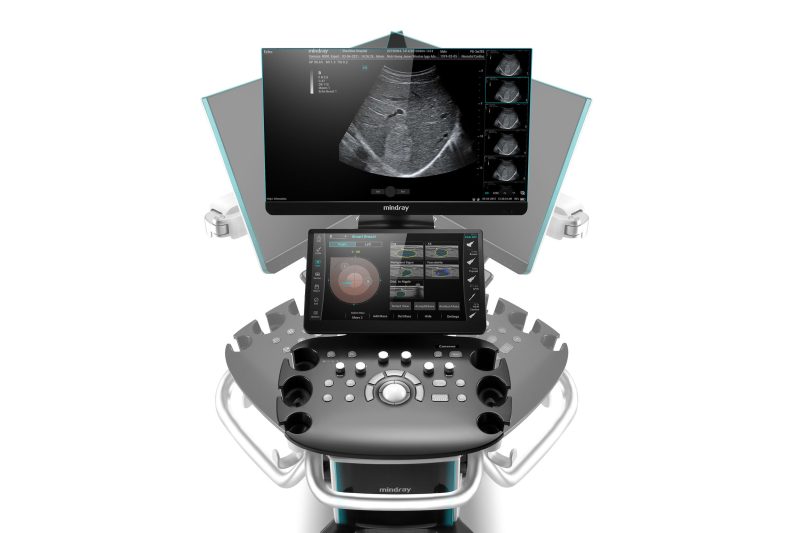

- Fully digital ultrasound system

- 21.5″ Full HD LED monitor, height and side adjustable, automatic brightness correction

- 13.3″ control touch panel, foldable, gesture control

The Mindray Consona N6 Ultrasound System is an advanced and compact ultrasound system designed for a wide range of clinical applications. With its high-quality imaging capabilities, it delivers exceptional resolution and depth penetration for accurate diagnostic evaluations. The Zone sonography platform is very different from conventional beamformer technology. Your advantages are an ultra-fast image build-up and a B-image that is completely focused from the near field to the depths. Focus on the image, the system will do the rest!

- 2 HD monitors: 21.5″ & 13.3 (touch).

- Bezel-less HD monitor for an immersive experience

- Full-HD touch screen with intuitive interaction